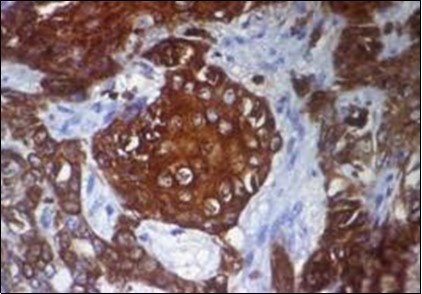

Granular arrangement of malignant cells and intercellular bridges are conspicuous with the demonstration of nuclear atypia, pleomorphism, prominent mitosis and tumour necrosis. A peripheral palisade is discernible within the cellular aggregates. Mitotic figures are common and can be quantified as up to 12 mitosis/ high power field. Tumour differentiation can prominently be of the ductal category with the demonstration of intra-cytoplasmic lumina. Comedo type tumour necrosis is evident along with foci of squamous differentiation The neoplasm is reactive to periodic acid Schiff ‘s (PAS) stain. (Figure 1, Figure 2, Figure 3, Figure 4, Figure 5, Figure 6, Figure 7, Figure 8, Figure 9, Figure 10, Figure 11, Figure 12, Figure 13.

Figure 1.Solid aggregates of tumour cells and duct structures in eccrine porocarcinoma (14).

Figure 3.Cohesive accumulations with numerous ductular articulations of carcinoma cells in eccrine porocarcinoma (15).

Figure 4.Cellular atypia, mitosis and focal necrosis in eccrine porocarcinoma(16).

Figure 5.Sweat glandular articulations and malignant cellular aggregates with cystic spaces in eccrine porocarcinoma(17).

Figure 6.Epidermal continuity with aggregates of atypical, solid and cystic epithelial cell nests in eccrine porocarcinoma (18).

Figure 7.Aberrant and malignant epithelium with cellular proliferation and pleomorphism in eccrine porocarcinoma with frequent mitosis(19).

Figure 8.Disseminated atypical epithelial cells with cellular and nuclear pleomorphism, hyperchromasia, indistinct cytoplasm, vesicular nucleoli and central keratinization in eccrine porocarcinoma(20).

Figure 9.Branches and cords of malignant epithelial cells in eccrine porocarcinoma with a superficial, abutting epithelium and mitotic figures(21).

Figure 10.Duct like configurations and atypical epithelial cells with prominent mitosis in eccrine porocarcinoma (22).

Figure 11.Eccrine porocarcinoma displaying cords and strands of atypical epithelial cells with glandular arrangements (23).

Figure 12.Immune reactivity to cyto-keratin (CK7) in eccrine porocarcinoma(24).

Figure 13.Immune reactivity to CK6 in eccrine porocarcinoma(25).